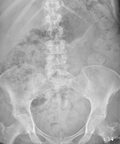

Патология толстого кишечника, связанная с длительным застоем каловых масс в кишечнике в результате постоянных нарушений моторной функции кишки. К запорам приводят пороки развития кишечника, рак толстой кишки, патология нервной системы, особенности питания с резким ограничением растительной пищи.

ДИАГНОСТИКА

Изучение истории болезни и медицинский осмотр не проводятся. Вообще никаких проверок за пределами физического необходимо. Иногда КТ, чтобы исключить другие, более серьезные причины.